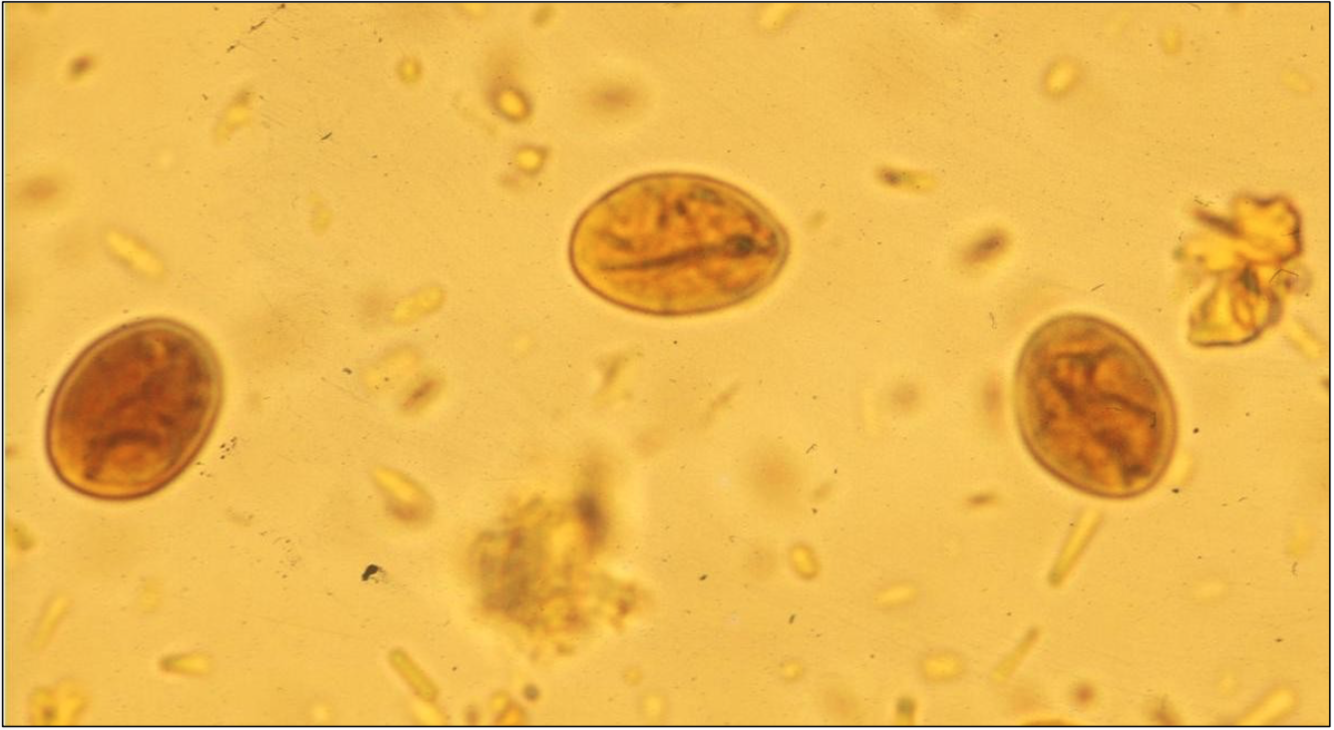

Giardia: kystes